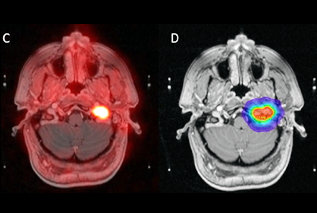

The U.S. Food and Drug Administration (FDA) has approved the radiopharmaceutical gallium-68 (Ga-68) DOTATATE for use with PET imaging.

The radioactive probe, marketed by Advanced Accelerator Applications (AAA) under the brand name Netspot, is intended to help locate tumors in adult and pediatric patients with the rare condition of somatostatin receptor-positive neuroendocrine tumors (NETs).

The uptake of Ga-68 DOTATATE can be seen in these tumors and a variety of other cancers, but may need to be confirmed by histopathology.